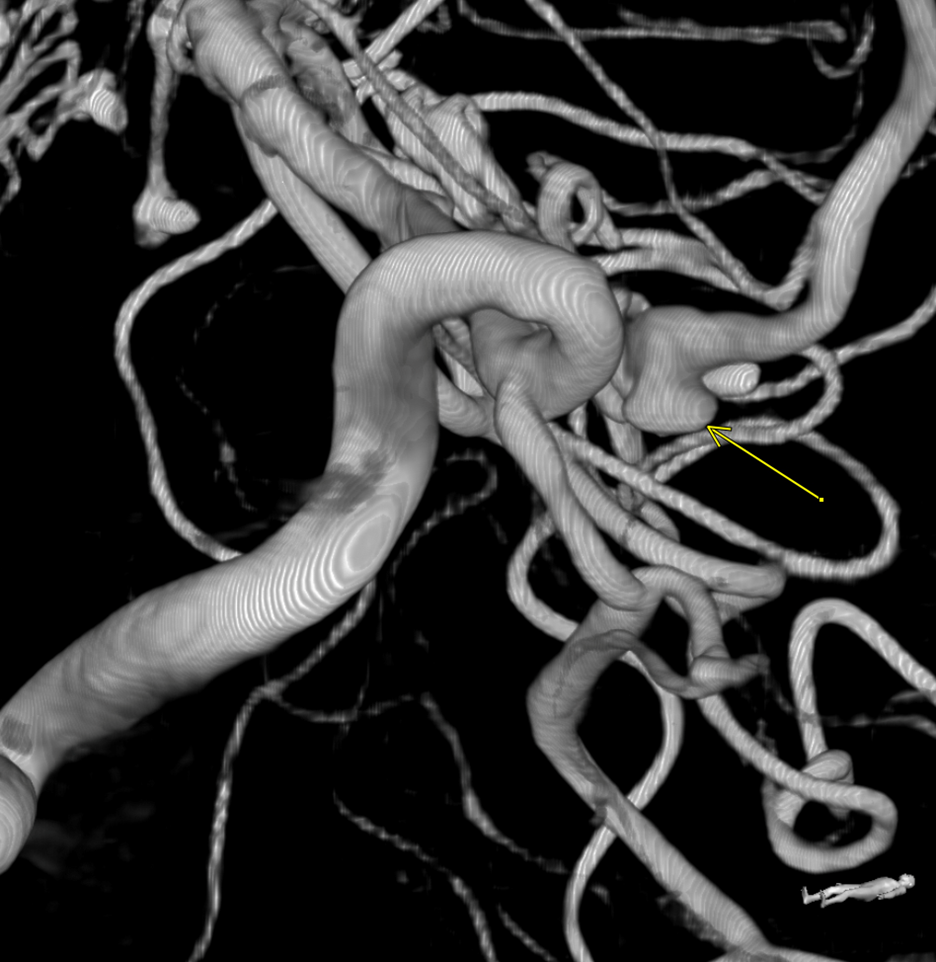

Subsequent digital subtraction angiography (DSA) was also negative for an aneurysm. A repeat angiogram conducted 7 days later revealed a dissecting pseudoaneurysm arising from the right A1 segment of the anterior cerebral artery, measuring approximately 5 mm with adjacent severe spasm at the A1 origin (Figures 3 and 4).

Figure 4. The DSA reconstructed image, again showing the pseudoaneurysm.

A CT of the head done 7 weeks following reconstruction showed stable ventricular size and no new hemorrhage. However, repeat angiography showed growth in the ectatic portion of the right A1 blood blister-like aneurysm (Figure 5), which was successfully treated with pipeline embolization (Figure 6). The 4-month follow-up revealed no evidence of recurrence and the patient has since made a full recovery.

Figure 5. The DSA demonstrating a blood-blister like aneurysm recurrence.